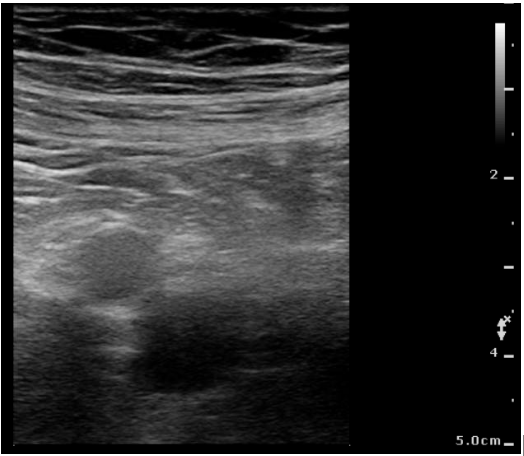

Relevant Test Results Prior to Catheterization

D-dimer was markedly elevated at 5.02 mg/L FEU. Laboratory data showed Hb 11.7 g/dL, PLT 167 K/¥ìL, WBC 6.73 K/¥ìL, and serum creatinine 2.10 mg/dL. Bedside POCUS demonstrated a non-compressible right femoral vein containing a floating thrombus. CT venography was deferred due to renal dysfunction. Right lower limb edema remained controlled under enoxaparin therapy.